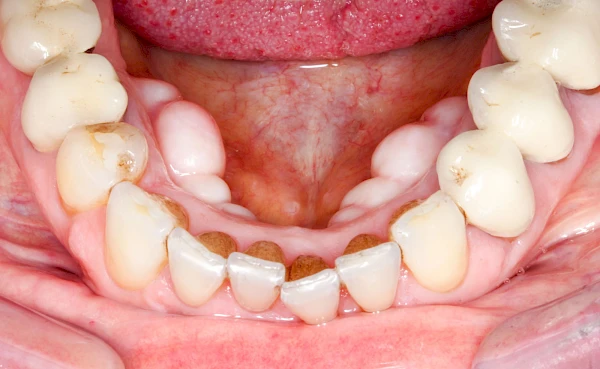

Überbeine im Bereich der Kiefer sind gar nicht so selten. Häufiger im Bereich der Seitenzähne unterhalb des Zahnfleisches, aber auch in der Mitte vom Gaumen. Überbeine haben in dem Sinne keinen Krankheitswert, müssen also nicht operativ entfernt werden, wenn diese nicht stören. Überbeine können ein Anzeichen für Knirschen und Pressen sein.